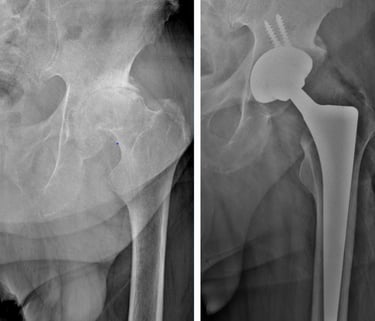

Displasia del desarrollo de cadera: es una alteración en la formación de la articulación de la cadera que está presente desde el nacimiento. Puede provocar que la cabeza del fémur no encaje bien en el acetábulo (la cavidad de la pelvis), lo que con el tiempo ocasiona dolor, cojera y desgaste temprano de la articulación. Su detección y tratamiento oportuno permiten prevenir complicaciones y preservar la función de la cadera.

Secuelas de displasia de cadera